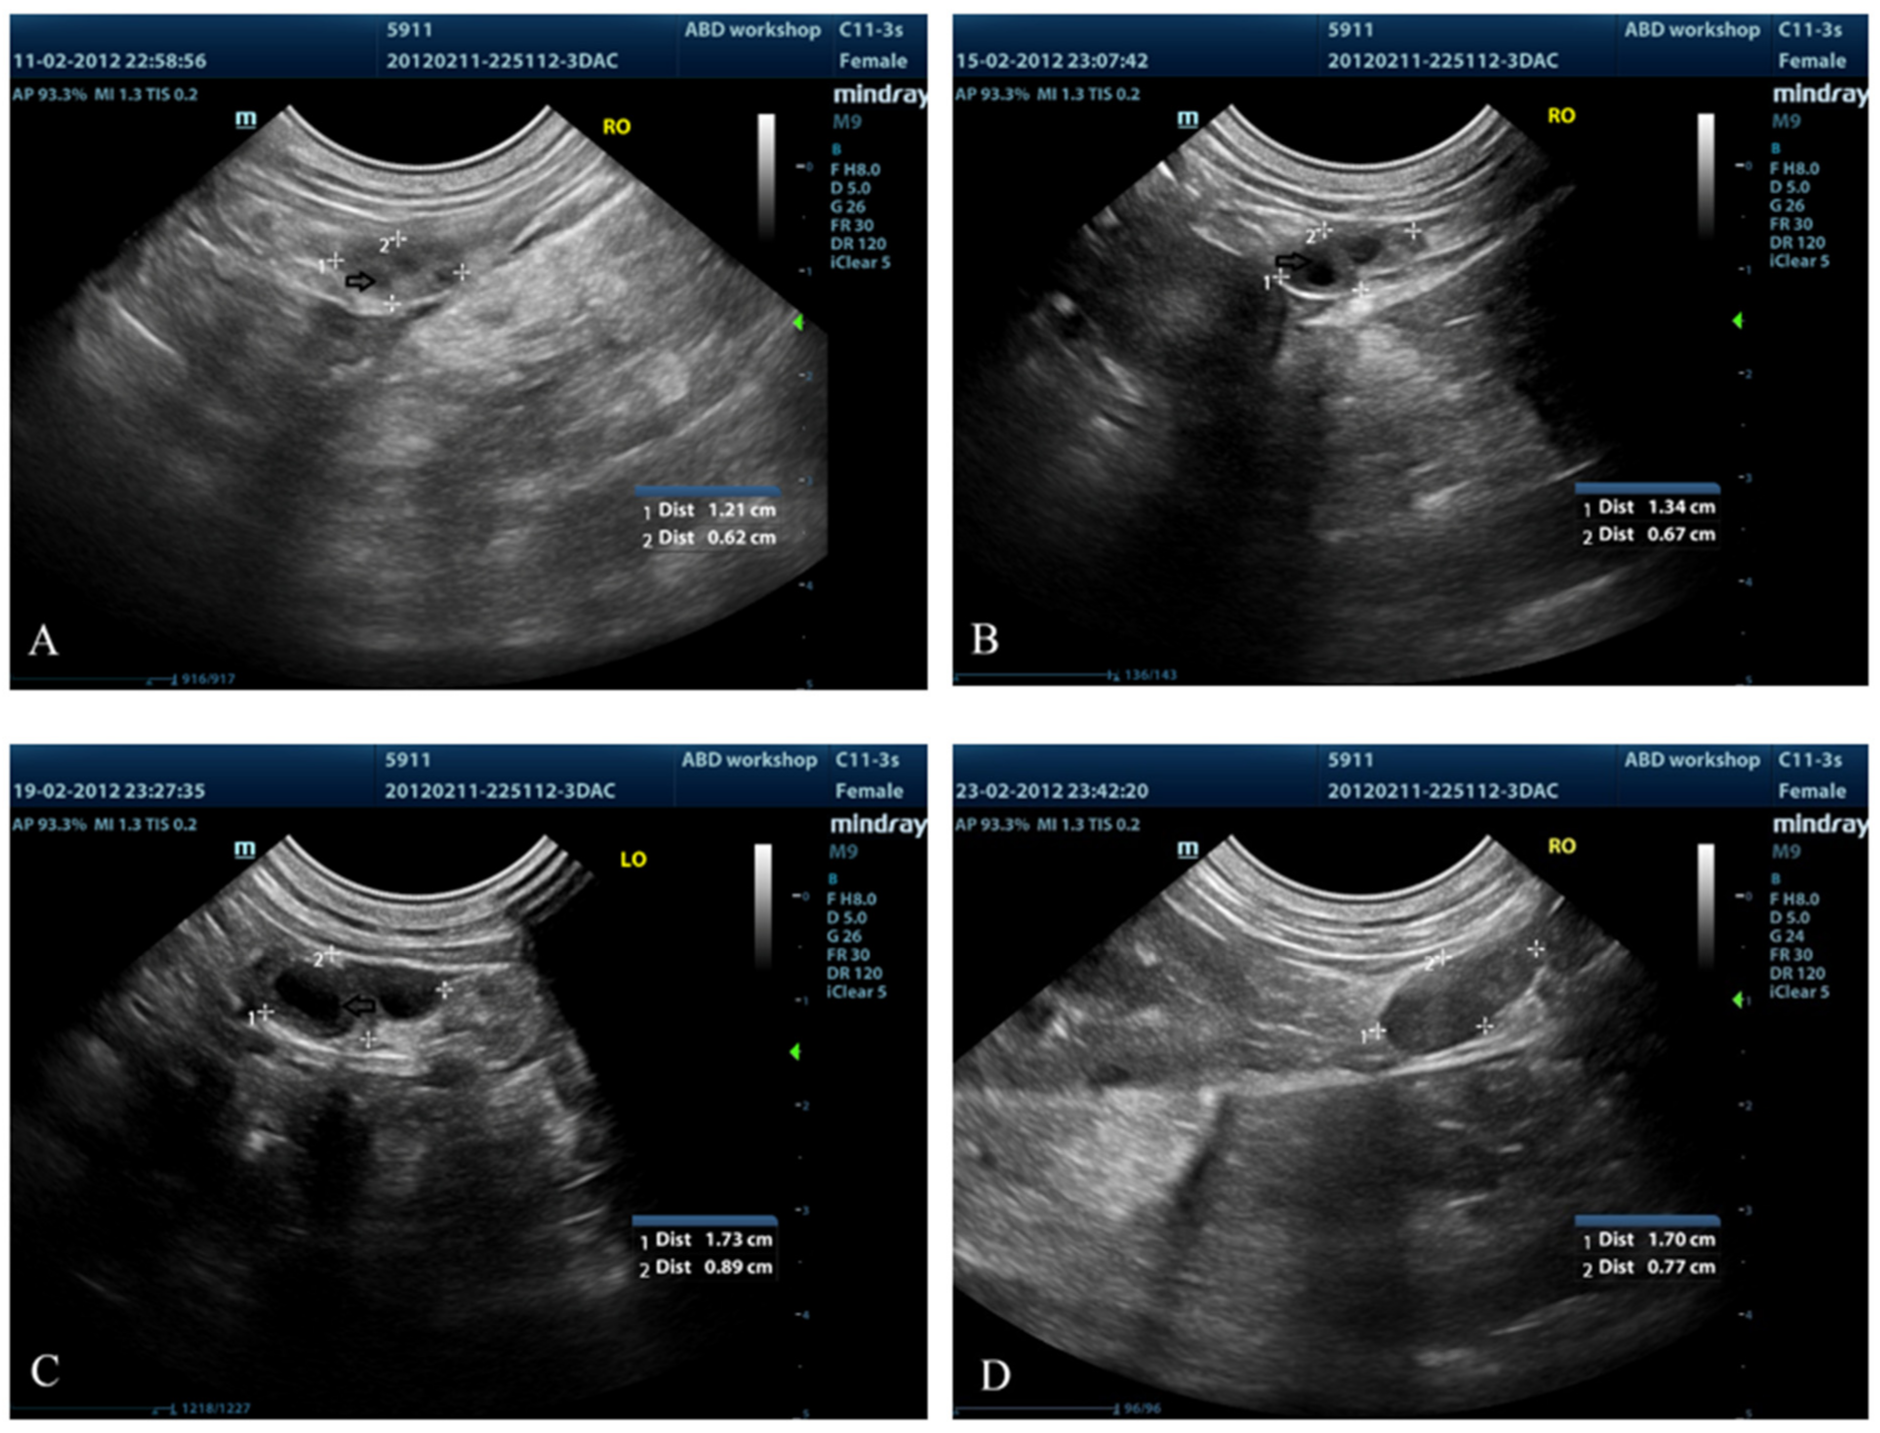

2.5. Ultrasonographic Examination of Ovaries

3.3. Ovarian Ultrasound

- Bergeron, L.H.; Nykamp, S.G.; Brisson, B.A.; Madan, P.; Gartley, C.J. An evaluation of B-mode and color Doppler ultrasonography for detecting periovulatory events in the bitch. Theriogenology 2013, 79, 274–283. [Google Scholar] [CrossRef]

- Wallace, S.S.; Mahaffey, M.B.; Miller, D.M.; Thompson, F.N.; Chakraborty, P.K. Ultrasonographic appearance of the ovaries of dogs during the follicular and luteal phase of the estrous cycle. Am. J. Vet. Res. 1992, 53, 209–215. [Google Scholar] [PubMed]